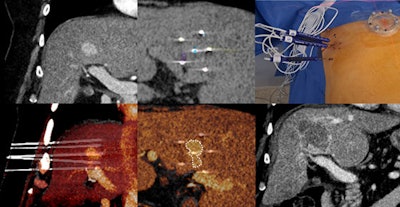

A second-year radiology resident inserts an irreversible electroporation (IRE) needle using Epione, the robotic-assisted platform from Quantum Surgical that supports interventional radiologists in treating inoperable or challenging early-stage tumors. Courtesy of Laurent Milot, MD, PhD.

Corresponding treatment of a central hepatocellular carcinoma (HCC) shows the precision achieved with the help of the robot, even for junior practitioners. Courtesy of Laurent Milot, MD, PhD.